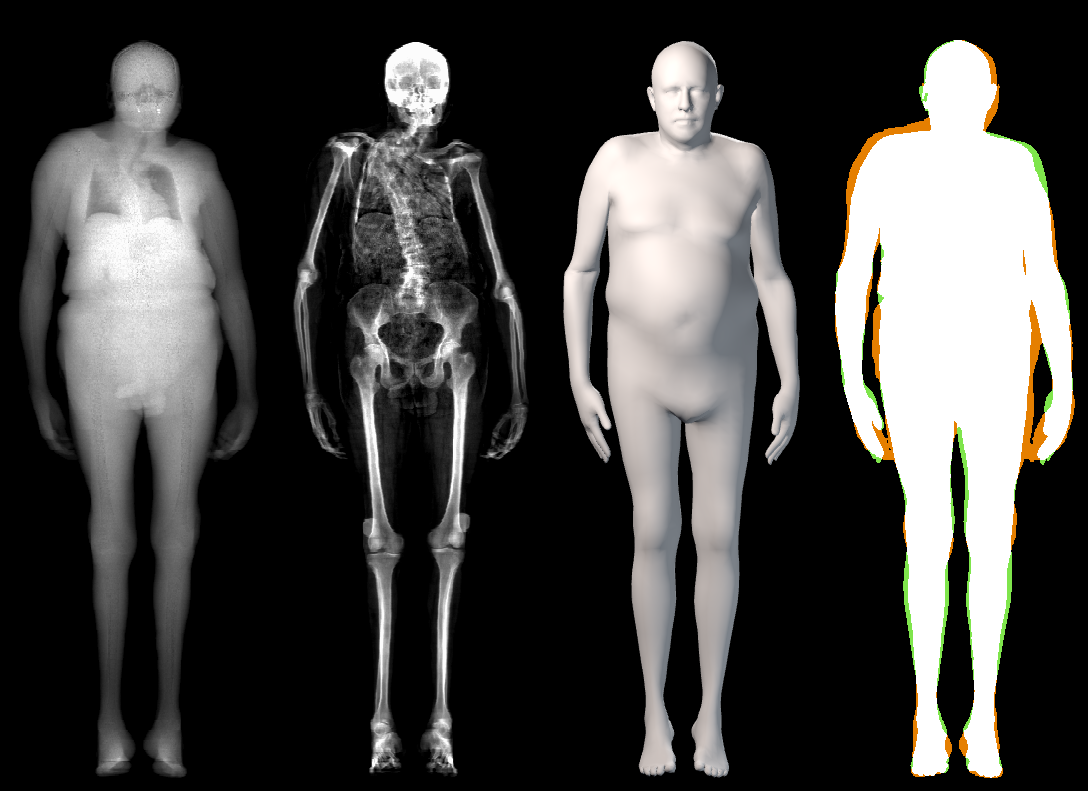

The key problem, however, is obtaining training data that simultaneously gives the inside and outside of the body in 3D. Most imaging technologies that simultaneously capture the inside and outside of the body use ionizing radiation, which is harmful to humans; e.g. Computed Tomography (CT) and X-rays. This means that such data is extremely limited, preventing learning-based methods. Our insight is to use dual-energy X-ray absorptiometry (DXA) data. DXA scans use low-dose X-rays to measure bone mineral density and body fat composition. The radiation level is so low that it is certified to be used on healthy patients for clinical studies, such as the UK Biobank [36]. In a DXA scan, two images are computed by combining two different energy levels: a soft-tissue image and a bone image (Fig. 2). In the silhouette of the body can clearly be seen, whereas reveals the structure and shape of the bones.

From the input images (, ), we compute the corresponding skin and skeleton segmentation masks (, ). For the skin mask , we threshold . As some small artifacts remain, mainly due to pixels in the lungs with low intensity values, we detect the closed contours on the image and fill in small areas. In Fig. 2 we show pairs of input and the obtained mask .

In our work, we use a simple heuristic to automatically segment the bone tissue in the bone images: we assume that the brightest pixels in each image belong to bone tissue. We empirically set for the male DXAs and for the female. As small artifacts remain (earrings, clothing, etc.), we remove small connected components with an area less than 50 pixels. Note that we do not claim to segment all bone tissues in the DXA images. While our segmentations are coarse, they capture the structure and location of the bones inside the body (as shown in Fig. 2); this is what we need to fit a 3D skeleton to them.

In this section we illustrate the alignment results of the STAR model on the DXA images. Those alignments were obtained with the optimization presented in Sec. 3.3 of the main paper. These results complement the quantitative evaluation reported in Sec. 5.1 of the main manuscript, where the intersection over union coefficient between the DXA mask and the computed skin silhouette is for females and for males. In Figure 14, we show the qualitative results. The color-coded images show that the skin registrations faithfully capture the DXA skin silhouettes.